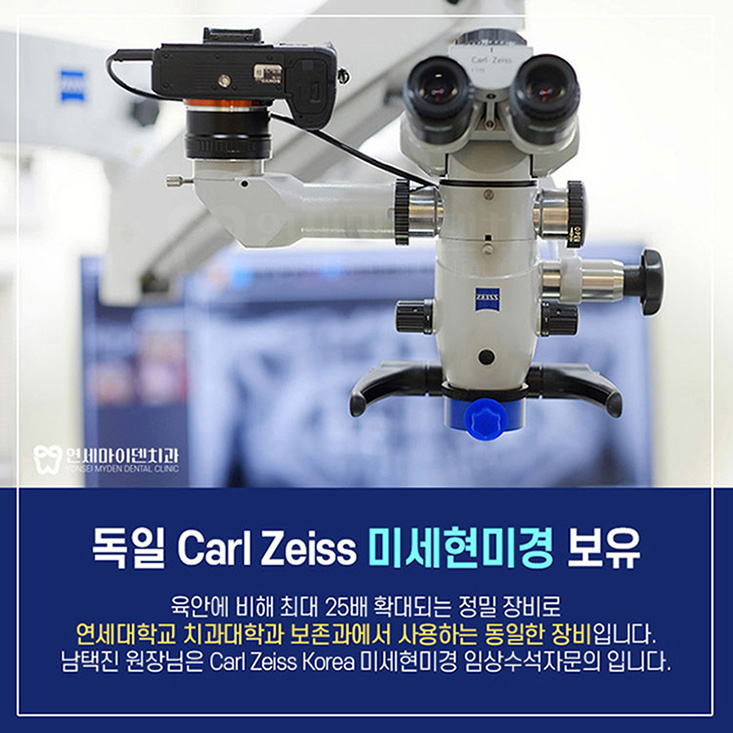

다시 한 번 내부를 들여다 보았습니다.

깨끗하게 내부 치료를 다시 하고 재감염이 없도록 레진코어까지 제대로 마무리했습니다.